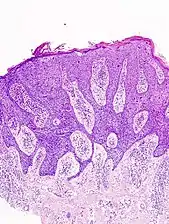

Characteristics

Histopathologically, the epidermis in SCC in situ (Bowen’s disease) will show hyperkeratosis and parakeratosis. There will also be marked acanthosis with elongation and thickening of the rete ridges. These changes will overly keratinocytic cells which are often highly atypical and may in fact have a more unusual appearance than invasive SCC. The atypia spans the full thickness of the epidermis, with the keratinocytes demonstrating intense mitotic activity, pleomorphism, and greatly enlarged nuclei. They will also show a loss of maturity and polarity, giving the epidermis a disordered or “windblown” appearance.

In situ disease

Bowen's disease is essentially equivalent to and used interchangeably with SCC in situ, when not having invaded through the basement membrane.[33] Depending on source, it is classified as precancerous[34] or SCC in situ (technically cancerous but non-invasive).[35][36] In SCC in situ (Bowen's disease), atypical squamous cells proliferate through the whole thickness of the epidermis.[33] The entire tumor is confined to the epidermis and does not invade into the dermis.[33] The cells are often highly atypical under the microscope, and may in fact look more unusual than the cells of some invasive squamous cell carcinomas.[33]

Invasive disease

In invasive SCC, tumor cells infiltrate through the basement membrane. The infiltrate can be somewhat difficult to detect in the early stages of invasion: however, additional indicators such as full thickness epidermal atypia and the involvement of hair follicles can be used to facilitate the diagnosis. Later stages of invasion are characterized by the formation of nests of atypical tumor cells in the dermis, often with a corresponding inflammatory infiltrate.[33]